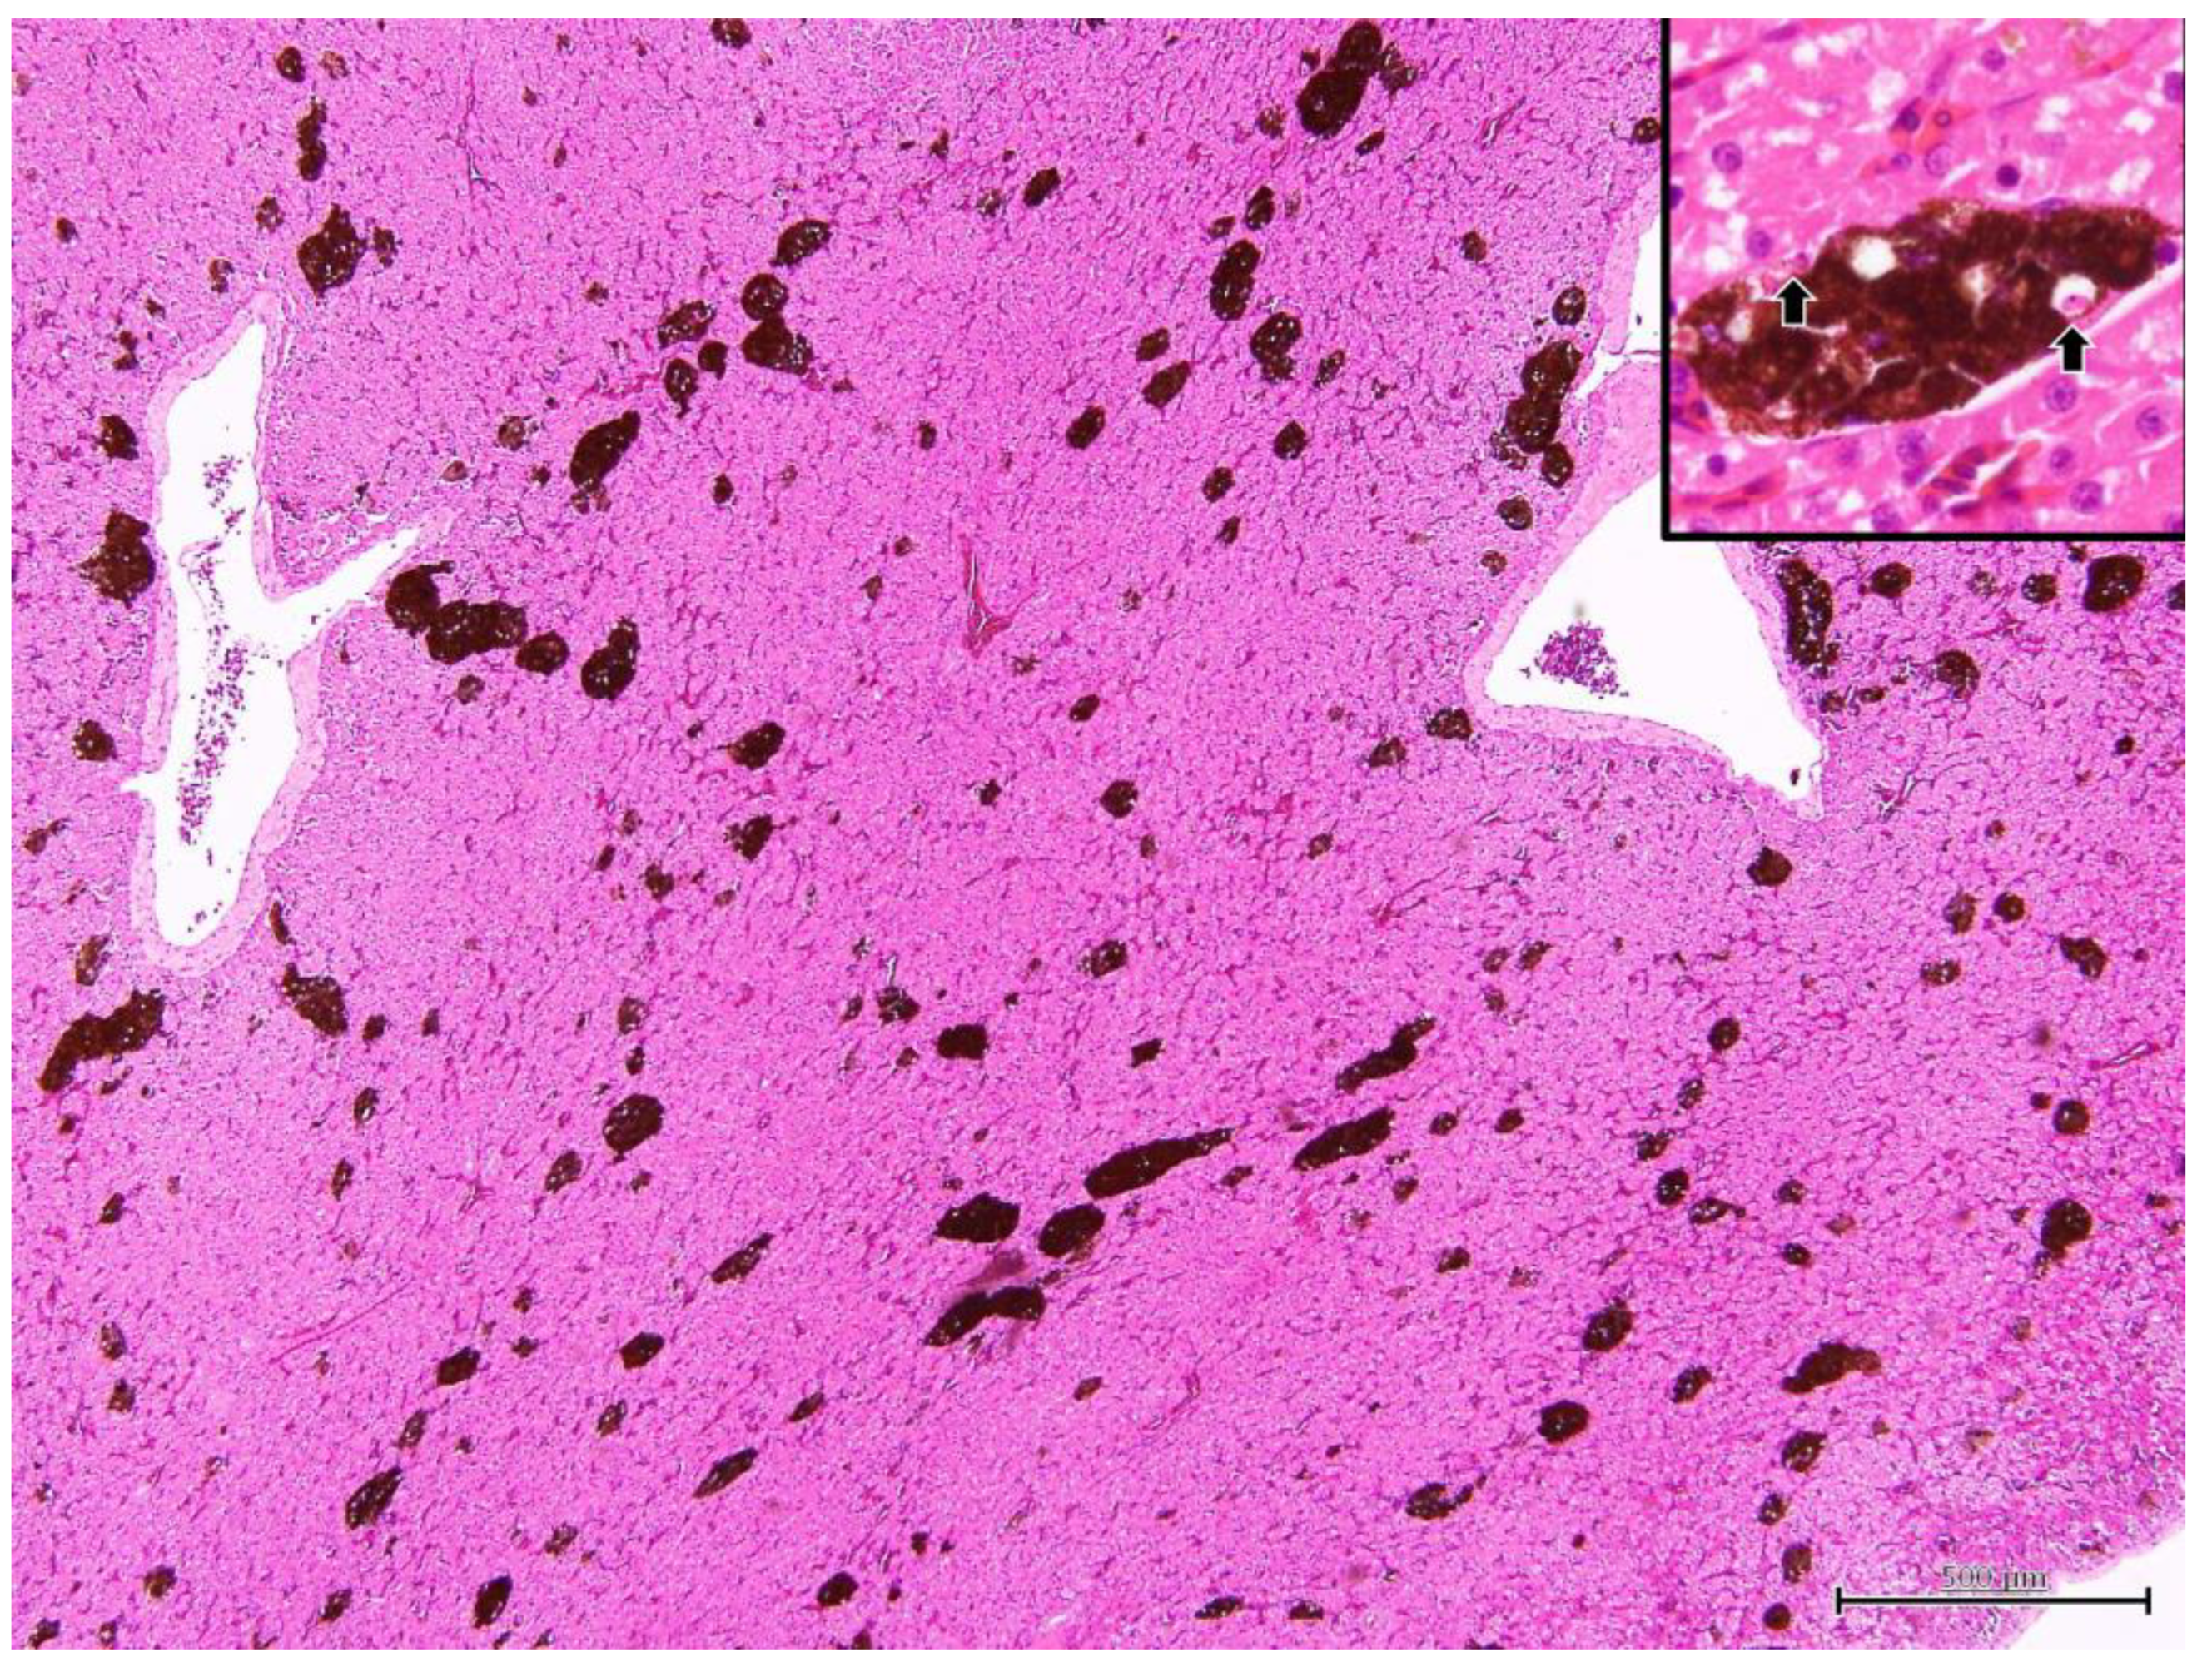

Iguana 1 was dehydrated and emaciated, with muscle loss on extremities and tail base. The ventral surface of the body, specifically the anterior one-third, showed extensive desquamation of the skin, exposing underlying tissues. Additionally, a significant amount of yellow-brown fibrinous exudate was observed adhering to the exposed areas. At necropsy, the fat pads were atrophic and no visceral fat was observed. The liver was diffusely dark green and slightly swollen withround edges (Figure 4). The serosa of the kidneys also revealed several dark green flat foci 0.1–1.0 mm in diameter. A heart blood smear was performed. The parasites consistent with hemococcidian sporozoites, as mentioned in Section 3.1.2, could be observed in erythrocytes and in one monocyte (Figure 5). Under histopathological examination, the melanomacrophage centers were markedly hyperplastic (Figure 6). Within the cytoplasm of the melanomacrophages, protozoa were noted individually or in clusters, being oval to fusiform in shape, approximately 9.0 × 1.7 μm in size, with a centrally located nucleus (arrow in inset of Figure 6). A focal area of the subserosa of the kidney also revealed the aggregation of melanomacrophages with the same intracytoplasmic protozoa.

Figure 6.

Under the section of the liver, the melanomacrophage centers (MMCs) are hyperplastic. Within the MMCs, numerous hemococcidan sporozoites can be observed in the cytoplasm of melanomacrophages (arrows in inset).

Liver stage (Figure 6): Under H&E stain section, the melanomacrophage center (MMC) was hyperplasic. Within the cytoplasm of the melanomacrophages, protozoa were noted individually or in clusters, oval to fusiform in shape, approximately 5.0 × 1.5 μm in size, with centrally located nuclei.